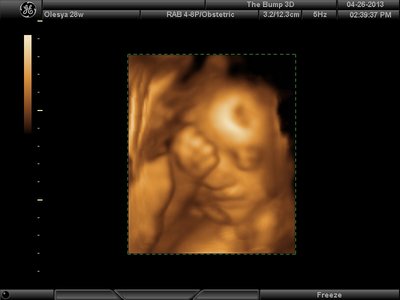

Еще одна, качество ужасное..

Вложения: |

image.jpg [ 60.32 КБ | Просмотров: 1181 ]